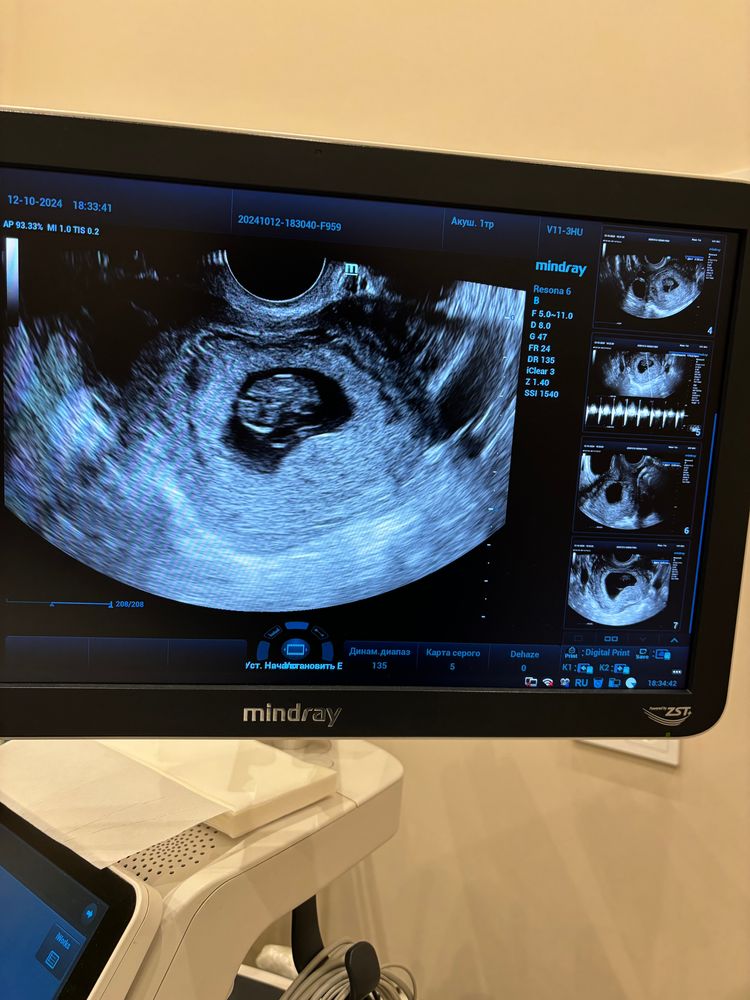

УЗИ, 8 недель

8 недель 1 день

тихонько растем, КТР 21 мм, первый раз слышала сердечко

ттт, все хорошо, надеюсь так будет и дальше, скоро-скоро первый скрининг через, месяц примерного)